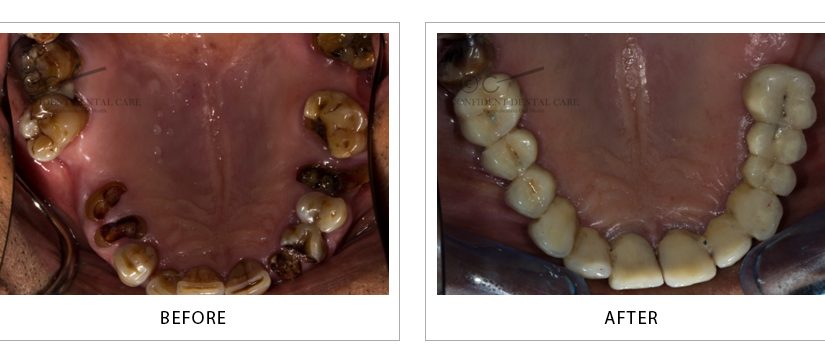

Full Mouth Implant